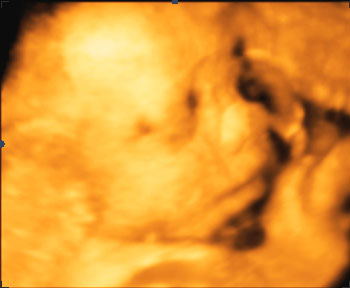

Sandra Skrevet 13. juni 2008 Forfatter #110 Skrevet 13. juni 2008 I dag ville knøttet vise ansiktet sitt og vi fikk 4 bilder (med litt forskjellig kvalitet vil jeg si da men ...). Endelig fikk vi se litt baby i all fall :-D Et av dem ble ganske bra, kan se om jeg får til å legge det ut her senere i dag. Det er vel lov det er det ikke? Vil aldri ha betalt 1500 kroner for dette selv en annen gang. Synes ikke det var verdt det, men det var jo bra å se at alt sto bra til med den lille på medisinske gjennomgangen selv om det strengt tatt ikke var nødvendig. Vi hadde jo sett det på den ordinære ULen også. Det var jo mamma som så gjerne ville dette da, så det var hun som spanderte dette også. I kveld skal hun få se bildene Etter UL-timen var jeg så kvalm! Det var nok fordi jeg hadde spist alt for mye søtt og snop på for kort itd for at lillemann i magen skulle våkne. Spiste først en bolle fylt med gult med sjokotrekk på toppen Den var jo kjempegod da. Så drakk jeg en masse appelsinuice, og etter det melkesjokolade. Fikk kjøpt meg nye gummistøvler i dag, svarte høye med snøring. Det skal visst regne i helgen, så vi får pakke med oss regntøy til kristiansand. Det kan bli et vått møte med kaptein sabetann og vennene hans... Nå skal jeg hente mini i barnehagen :-D

Sandra Skrevet 13. juni 2008 Forfatter #111 Skrevet 13. juni 2008 Her kommer det et bilde fra Ultralyden i dag. :-D

monja Skrevet 13. juni 2008 #112 Skrevet 13. juni 2008 Se der er lille mannen ja. Synes nesten de er skumle disse 3D bildene. Ligner han på storebror? Så godt at dere fikk noen bilder iallefall

Sandra Skrevet 13. juni 2008 Forfatter #113 Skrevet 13. juni 2008 Synes egentlig utseende endrer seg fra bilde til bilde.. Men det er jo litt moro å se at det er en ordentlig baby der inne :-D

Gjest Indo Skrevet 13. juni 2008 #114 Skrevet 13. juni 2008 OI! Så et tydelig ansikt der ja..Tenk, snart skal du møte det ansiktet på "ordentlig" :rødme: God helg=)